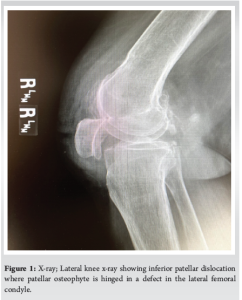

The patient is an 85-year-old female who presented 3 weeks after suffering acute onset right knee pain after a fall at home onto her bent knee. She was unable to bear weight or extend her knee since the injury and was stuck in 80° of flexion. Initial work-up at an outside institution included radiographs and magnetic resonance imaging (MRI) which revealed an inferior patella dislocation where a superior patellar osteophyte hinged on a defect in the lateral femoral condyle (Fig. 1). MRI showed an intact quadriceps and significant patellofemoral osteoarthritis. In the office, a closed reduction maneuver was performed. The patient was placed supine, and the knee was injected with 2% lidocaine. The knee was then hyperflexed while inferiorly translating the patella out of the osteochondral defect (OCD) after which the knee was brought back into extension. Clinically, the patella was reduced with immediate resolution of pain. However, the patella dislocated while being flexed during post-reduction X-rays requiring a second reduction maneuver. The reduction was maintained the second time and confirmed on radiographs. The patient was made weight-bearing as tolerated with a walker and knee immobilizer. One week later, her pain was resolved and radiographs in the office confirmed maintenance of reduction. She remained weight-bearing as tolerated and was encouraged to do straight leg raises to improve quadriceps strength. The knee immobilizer was maintained. At three weeks after reduction, she was pain-free and able to flex and extend from 0 to 90°. She was started on formal physical therapy and given a hinged knee sleeve with instructions to not flex beyond 90°. At 7 weeks, she had regained full range of motion and quadriceps strength. The hinged knee sleeve was discontinued. Two days after discontinuing the knee brace, she dislocated in her sleep. The knee was again injected but two attempted closed reductions in the office were unsuccessful and operative intervention was performed that evening. After intubation in the operating room, she remained stuck in flexion. She subsequently underwent arthroscopic takedown of the patellar osteophyte and debridement of the lateral trochlear OCD with the resolution of her dislocation (Fig. 2 and 3). An accessory superomedial portal allowed easier access to the patellar osteophyte. The patient was discharged home the following day, weight bearing as tolerated, with an ace bandage but no immobilization. She received home physical therapy. At one-month follow-up, the patient was pain-free, had a good range of motion, and was very satisfied with the outcome. Radiographs showed maintenance of reduction. At the final follow-up 12 months later, the patient remains pain-free with no recurrence of the dislocation.

There have been several case reports describing inferior patellar dislocation in elderly patients [2-11]. Treatment of these injuries has ranged from closed reduction to arthroscopic or open surgical treatment. We present the first late recurrence of inferior patellar dislocation in an elderly patient after initial treatment with closed reduction and immobilization. Multiple studies have shown successful treatment of type II inferior patellar dislocations with closed reductions and 3–4 weeks of immobilization [2-7]. Closed reduction under general anesthesia was performed in two cases [3,4]. Reduction under IV sedation in the emergency department was performed in two cases [2,6]. Intra-articular injection was used in one case and a peripheral nerve block was used in another [5,7]. While follow-up varied in these cases, there was no reported recurrence of dislocation. In our case, initial closed reduction was accomplished after intra-articular injection via hyperflexion of the knee and a downward force on the patella followed by gradual knee extension. Several other studies reported similar reduction mechanisms [2,4,5,7,8]. Wight et al. reported a different mechanism that included flexing the knee to 90°, applying an anterior drawer force to the tibia, and then counter-pressure to the inferior pole of the patella [6]. Two studies reported a recurrence of the dislocation after the initial closed reduction [8,10]. Syed and Ramesh reported a case of a patient who re-dislocated 8 days after the initial closed reduction [10]. The patient was immobilized in a knee splint for only 6 days and then dislocated while in bed. Subsequent closed reduction was unsuccessful, and she was treated with osteophyte removal via an open medial parapatellar approach. Barlow et al. reported a recurrent dislocation 1 day after the initial closed reduction as the patient was unable to tolerate her splint [8]. She was treated with arthroscopic resection of a patellar osteophyte and smoothing of the lateral femoral condyle. In our study, the patient had an immediate initial recurrence of her dislocation while being flexed during her post-reduction X-rays. While the second reduction was successful and maintained for 7 weeks, repeat dislocations may suggest increased instability that would benefit from surgical treatment. Two additional studies reported failed initial attempts at closed reduction resulting in operative treatment [9,11]. Shivarathre and Keys reported a unique case of inferior patellar dislocation 12 months after total knee arthroplasty without patellar resurfacing [9]. This case was successfully treated through open debridement of osteophytes. Zimmermann et al. reported a case of failed closed reduction treated successfully with arthroscopic debridement [11]. Yoshioka et al. reported two cases, one of which they performed open removal of osteophyte and plate fixation of a lateral femoral condyle fracture even after successful closed reduction [7]. The differential diagnosis of an acute locked knee is broad and work-up relies on history, physical exam, and diagnostic tests, which often include an MRI [1,12]. In our case, the patient presented with a locked knee and patella baja. While this clinical scenario often points towards a quadriceps tendon rupture, the unique appearance of the lateral knee X-ray indicates inferior patellar dislocation (Fig. 1). In fact, the quadriceps tendon was intact in all of the reported cases of type II inferior patellar dislocations. In the case of an elderly patient presenting with acute locked knee and patella baja, inferior patellar dislocation must be considered. Initial work-up should include AP and lateral X-rays of the knee. A lateral view demonstrating a superior patellar osteophyte hinged on the femoral condyle is pathognomonic of this injury and obviates the need for an MRI. Closed reduction under intra-articular block or sedation should be attempted and confirmed via AP and lateral knee X-rays. Even if closed reduction is successful, however, arthroscopic surgery to debride the patellar osteophyte and smooth the femoral condyle should be considered. This minimally invasive treatment allows early mobilization and limits the chance of recurrence.